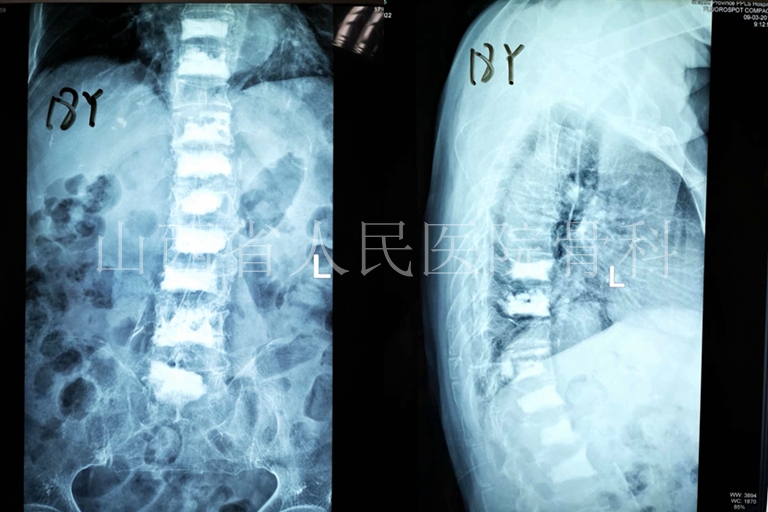

患者于2018年再次因压缩骨折入院。

2018年5月再次因腰背疼痛住院

2018年5月对L3-5椎体行PKP治疗